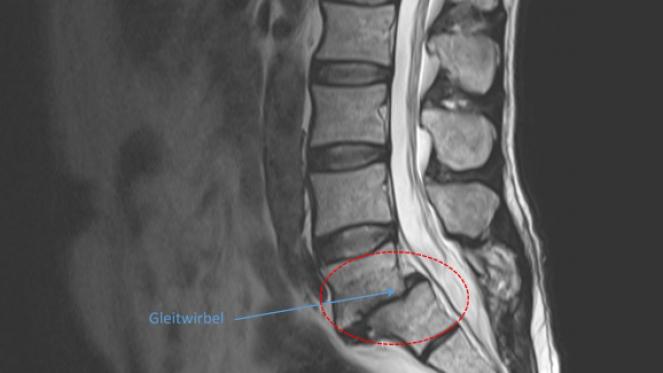

Gleitwirbel (Spondylolisthesis)

Spondylolisthesis wird in der Umgangssprache auch als Wirbelgleiten bezeichnet.

Sie ist in den meisten Fällen ein Ausdruck der Instabilität eines oder mehrerer Segmente der Wirbelsäule. Je nach Grad des Gleitens kann es zu Spinalkanalverengungen mit Nervenwurzelkompression und damit verbundenen Schmerzen und Ausfallerscheinungen (Sensibilitätsstörung, Lähmungen, Blasenmastdarmstörungen) führen.